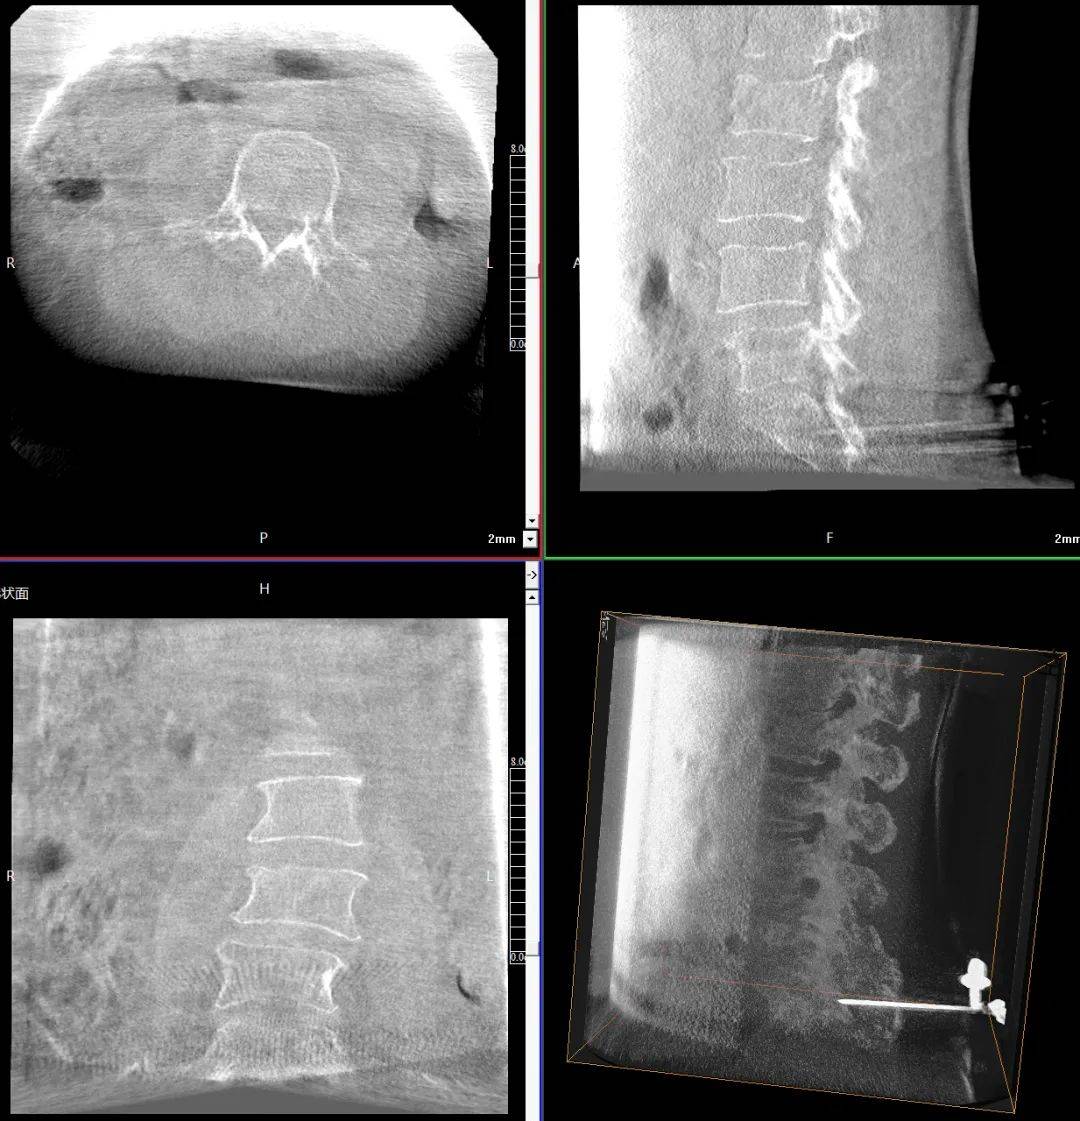

臨床表現(xiàn):患者主訴腰背部劇烈疼痛,活動受限;查體證實(shí)腰背部局部壓痛、叩擊痛明顯,尤其在受累椎體區(qū)域;影像學(xué)檢查顯示多節(jié)段椎體壓縮性骨折,椎體高度明顯降低,椎體形態(tài)不規(guī)則,椎體扭曲畸形,椎弓根狹窄。

患者術(shù)前影像